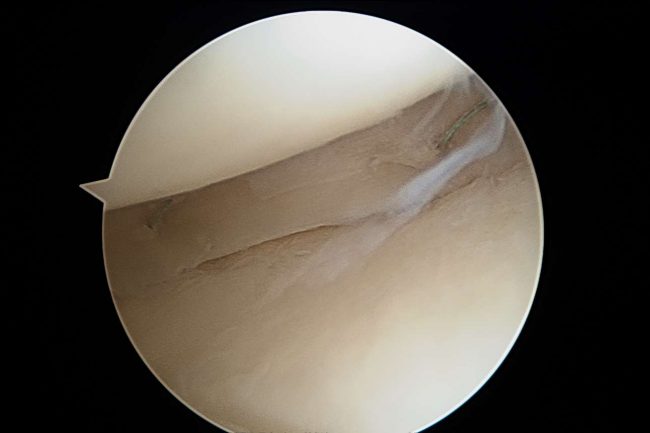

Ból kolana to jeden z najbardziej niewdzięcznych problemów, z jakimi zgłaszają się do ortopedy pacjenci. Dotyka zarówno młodszych, jak i starszych pacjentów.